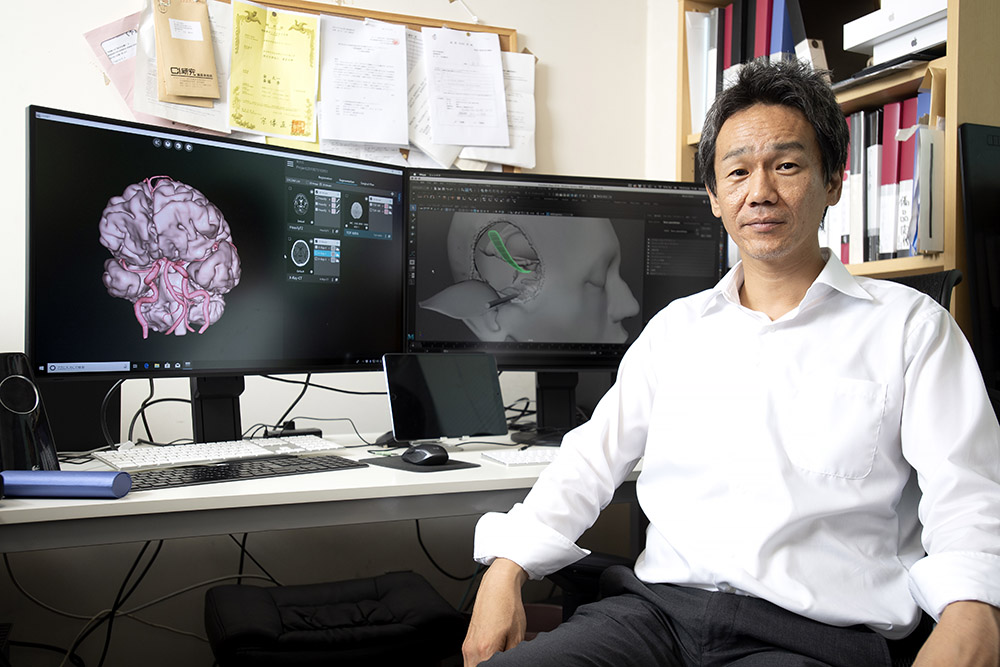

脳神経画像解剖ナビゲーション: 正常・変異・異常との比較で読影。脳の機能解剖とリハビリテーション | 金子 唯史 |本 | 通販 | Amazon。脳神経画像解剖ナビゲーション: 正常・変異・異常との比較で読影。金芽ロウカット玄米 2kg x4袋 東洋ライス。「脳神経画像解剖ナビゲーション = NAVIGATION OF IMAGING ANATOMY:CENTRAL NERVOUS SYSTEM : 正常・変異・異常との比較で読影に役立つ!」岡本 浩一郎 / 岡本 浩一郎定価: ¥ 9400#岡本浩一郎 #岡本_浩一郎 #岡本浩一郎 #岡本_浩一郎 #本 #自然/医療・薬学・健康○ 裁断について業者による裁断後の商品です。脳神経画像解剖ナビゲーション 正常・変異・異常との比較で読影。裁断済みのため、商品の状態は\"全体的に悪い\"にしています。ケーススタディで学ぶ 脳動脈瘤クリッピングの5ステップ - 株式。裁断について御理解のある方のみでお願い致します。メジカルビュー社|脳神経外科|エッセンシャル頭蓋底外科[Web。○ その他状態についてマーカーや書き込みはなしですが、素人検品である旨をご承知おき下さい。脳卒中後の病的な痛みに関連する大脳皮質の縮小信号を検出。スキャナ読み込みの段階でページの入れ替わりが稀にありますが、抜けはございません。01 脳のvascular territoryと脳葉の画像解剖 | 画像診断情報。ご確認ください。リハに活かす!機能解剖から学ぶ脳画像の読み方〜症状・経過。○ その他注意点返品・交換は承っておりません。NEXT FIELD 5:異分野間の連携が革命を起こす〜Mayaを操る脳神経。ご了承ください。Untitled Page。素人管理であることをご理解の上、ご購入ください。脳手術 AIシミュレーター『Hana』 – ポケクエ。他の商品と同時購入でしたら割引いたします。産科と婦人科増刊号 ホルモン療法 裁断すみ。その他なにかご要望ありましたら、気軽にコメントください。世界の見方の転換1、2、3。